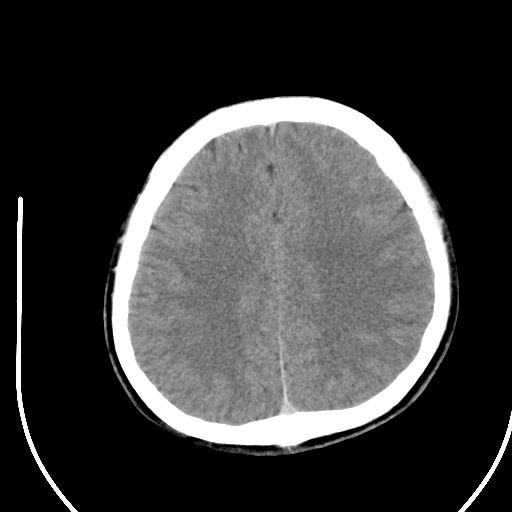

标题: CT28158:男,27Y。头痛数月,左顶叶血管瘤。 [打印本页]

标题: CT28158:男,27Y。头痛数月,左顶叶血管瘤。

海绵状血管瘤

考虑左顶叶海绵状血管瘤,建议mr检查。

左侧额叶海绵状血管瘤可能性大;建议行mri检查。

考虑血管畸形,因其周可见水肿,不除外感染性病灶。建议mri检查。